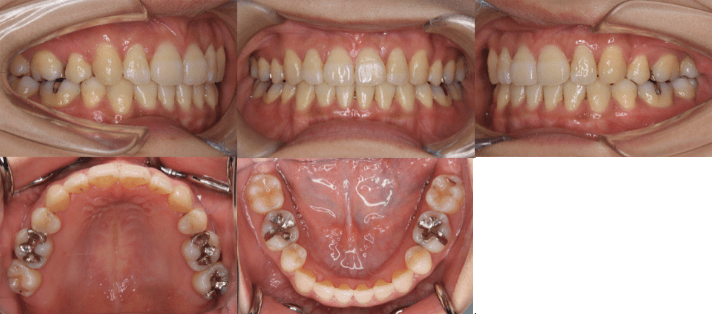

• 初診時年齢:25歳7ヶ月

• 主訴:前歯のガタガタ

• 診断:交叉咬合を伴う叢生症例

• 治療内容:小臼歯4本を抜歯した後、インビザラインを使用して主訴である叢生の改善を行いました。

• 治療期間:2年

• リスク:矯正治療による歯の移動に伴う痛み、歯根吸収、虫歯

• 費用:80万円